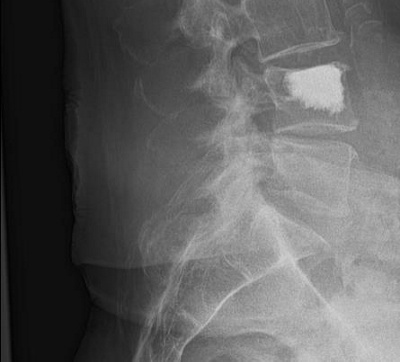

Rückenschmerzen

Am Rücken können unterschiedliche Strukturen zu Schmerzen führen. Um Rückenschmerzen gezielt individuell behandeln zu können, werden neben der genauen Befragung (Anamnese) und der klinischen Untersuchung bildgebende Verfahren wie Röntgen oder MRT/MRI (Magnetresonanztomographie) eingesetzt. Zur Schmerzkontrolle sind gezielte Infiltrationen unter Röntgen, Ultraschall und CT (Computertomographie) möglich. Neben der Schmerzkontrolle mittels Infiltration/Medikamenten ist für einen langfristigen Erfolg meistens individuelles Training wichtig.